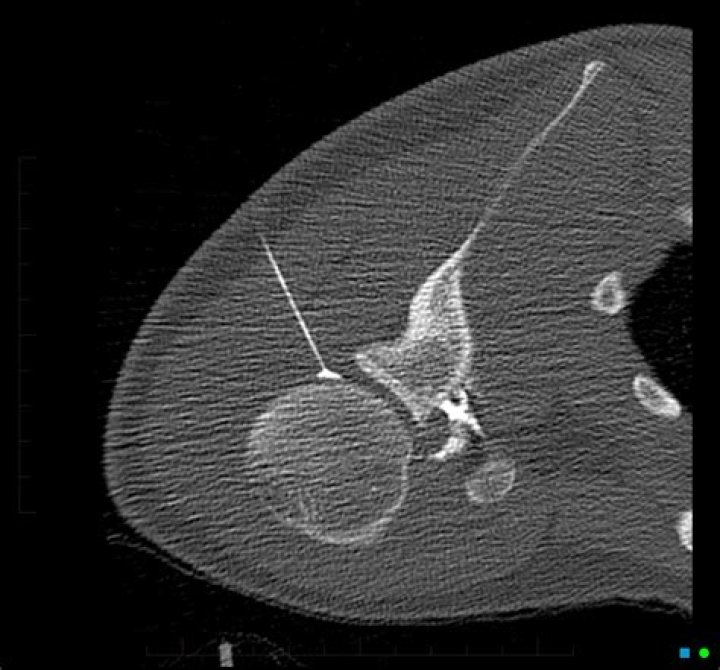

An arthrogram is performed to evaluate the structure and function of extremity joints, such as the shoulder, elbow, wrist, hip, knee or ankle. The procedure can help determine the need for treatment, including surgery or joint replacement.

An arthrogram provides a clear image of the soft tissue in the joint (e.g. ligaments and cartilage) so that a more accurate diagnosis about an injury or cause of a symptom, such as joint pain or swelling, can be made.

An Arthrogram uses fluoroscopy and an MRI to specifically diagnoses injuries in the joint structures that an MRI alone would likely miss. MRIs can be ordered with contrast that is delivered intravenously, while an Arthrogram has contrast needle-guided directly into the injured joint.